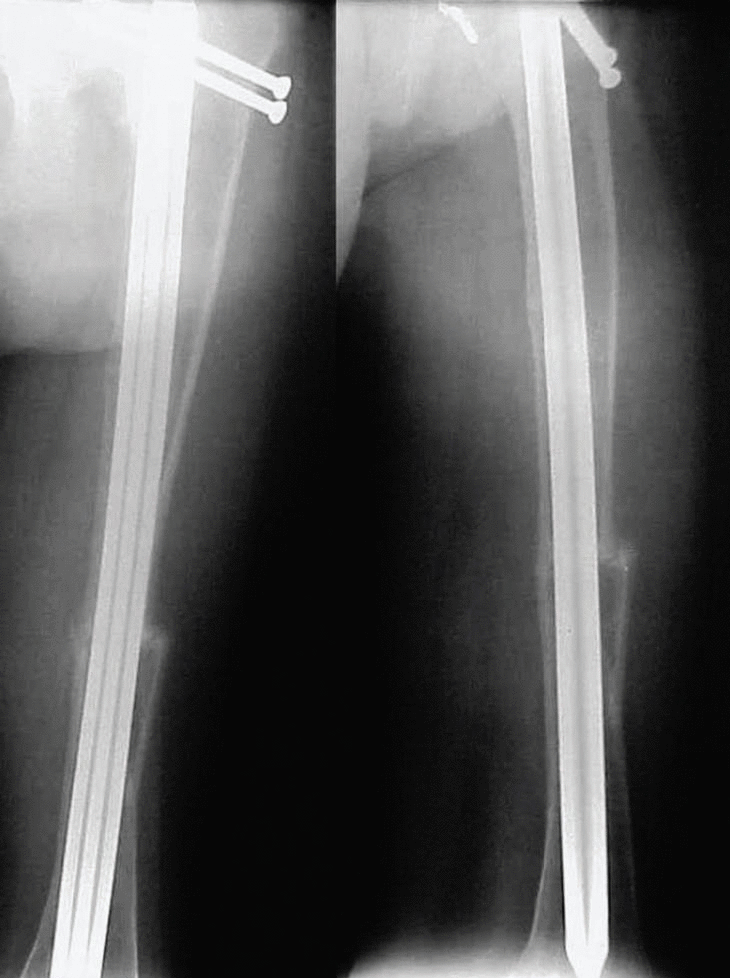

Se trata de un varón de 35 años que ingresa en la Sala de Urgencias del hospital Universitario de Los Andes (Mérida, Venezuela) con un cuadro clínico y radiológico de fractura de la diáfisis femoral izquierda, secundario a un trauma menor (golpe con una linterna de mano) (fig. 1).

Fig. 1. Fractura de la diáfisis femoral, trazo transverso. Espongialización de las corticales.